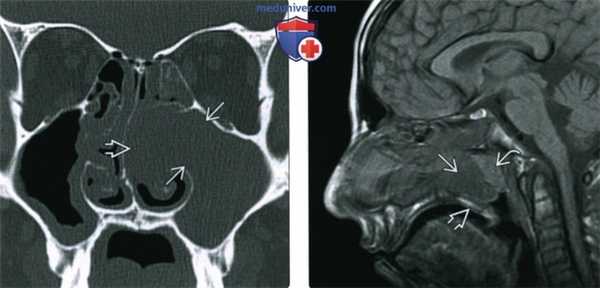

(Слева) При аксиальной «костной» КТ определяются типичные признаки АХП. Пневматизация правой верхнечелюстной пазухи снижена, визуализируется полиповидное мягкотканное образование, пролабирующее в полость носа. Сзади полип пролабирует через хоану в носоглотку.

(Справа) При аксиальной МРТ Т2 FS у ребенка определяется гиперинтенсивный АХП слева. Видны антральный и носоглоточный ва компоненты. АХП гиперинтенсивнен по сравнению с нижней носовой раковиной.

(Слева) При корональной МРТ STIR визуализируется типичный АХП, распространяющийся через устьев в полость носа. Внутриносовой компонент ва определяется изнутри от гипоинтенсивной нижней носовой раковины.

(Справа) При аксиальной МРТ Т1С+ FS визуализируется гантелеобразный назохоанальный полип, блокирующий хоанальные отверстия и заполняющий носоглотку. Вокруг образования определяется лишь периферическое контрастное усиление. Обратите внимание на ретенционные кисты, а верхнечелюстных пазухах.